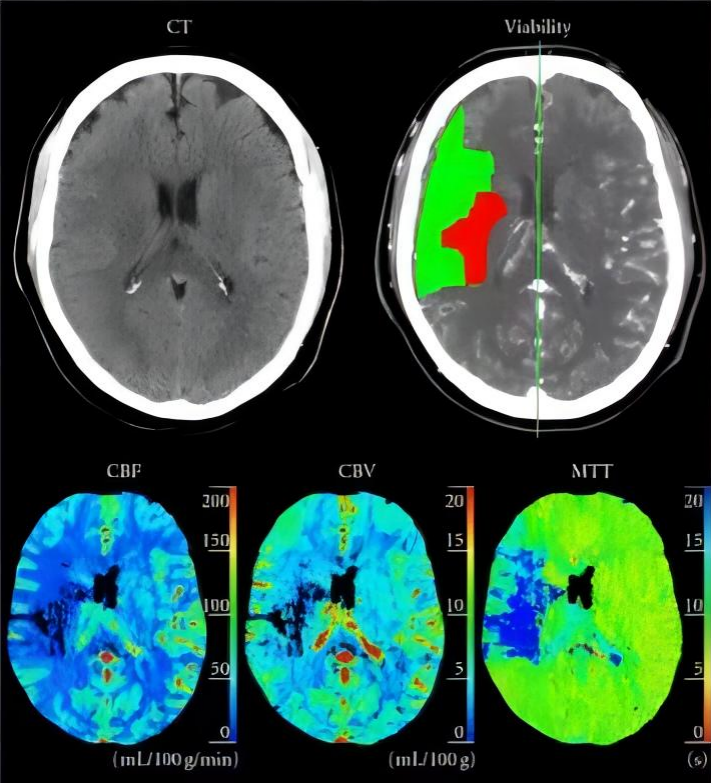

急性缺血性腦卒中CT灌注早期診斷